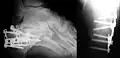

Le calcanéus peut subir des fractures.

Radio d'une fracture comminutive du calcanéum